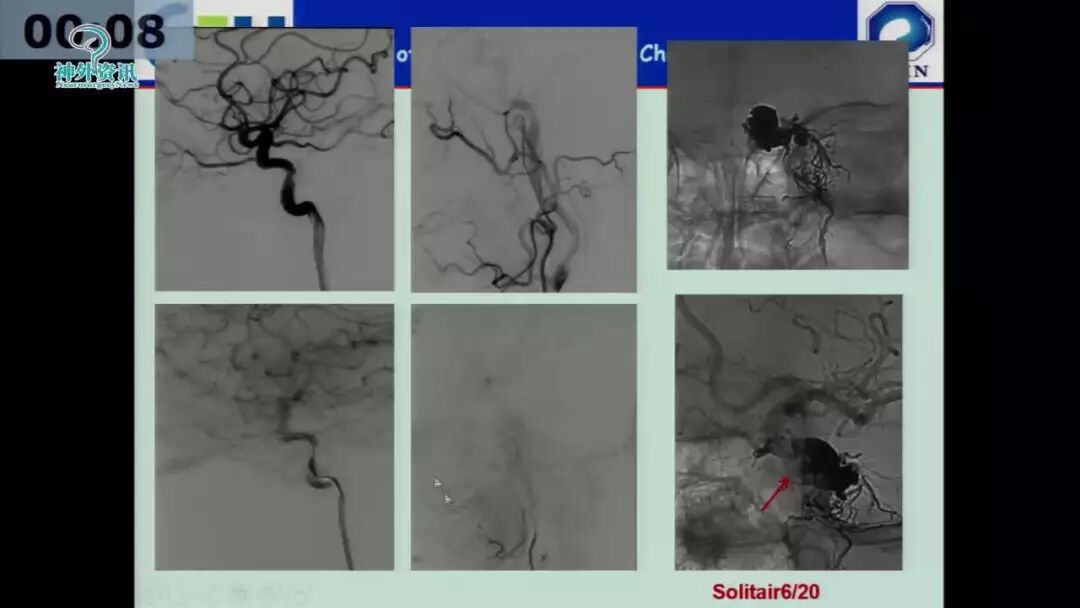

许奕教授:海绵窦区脑膜动静脉瘘的介入治疗